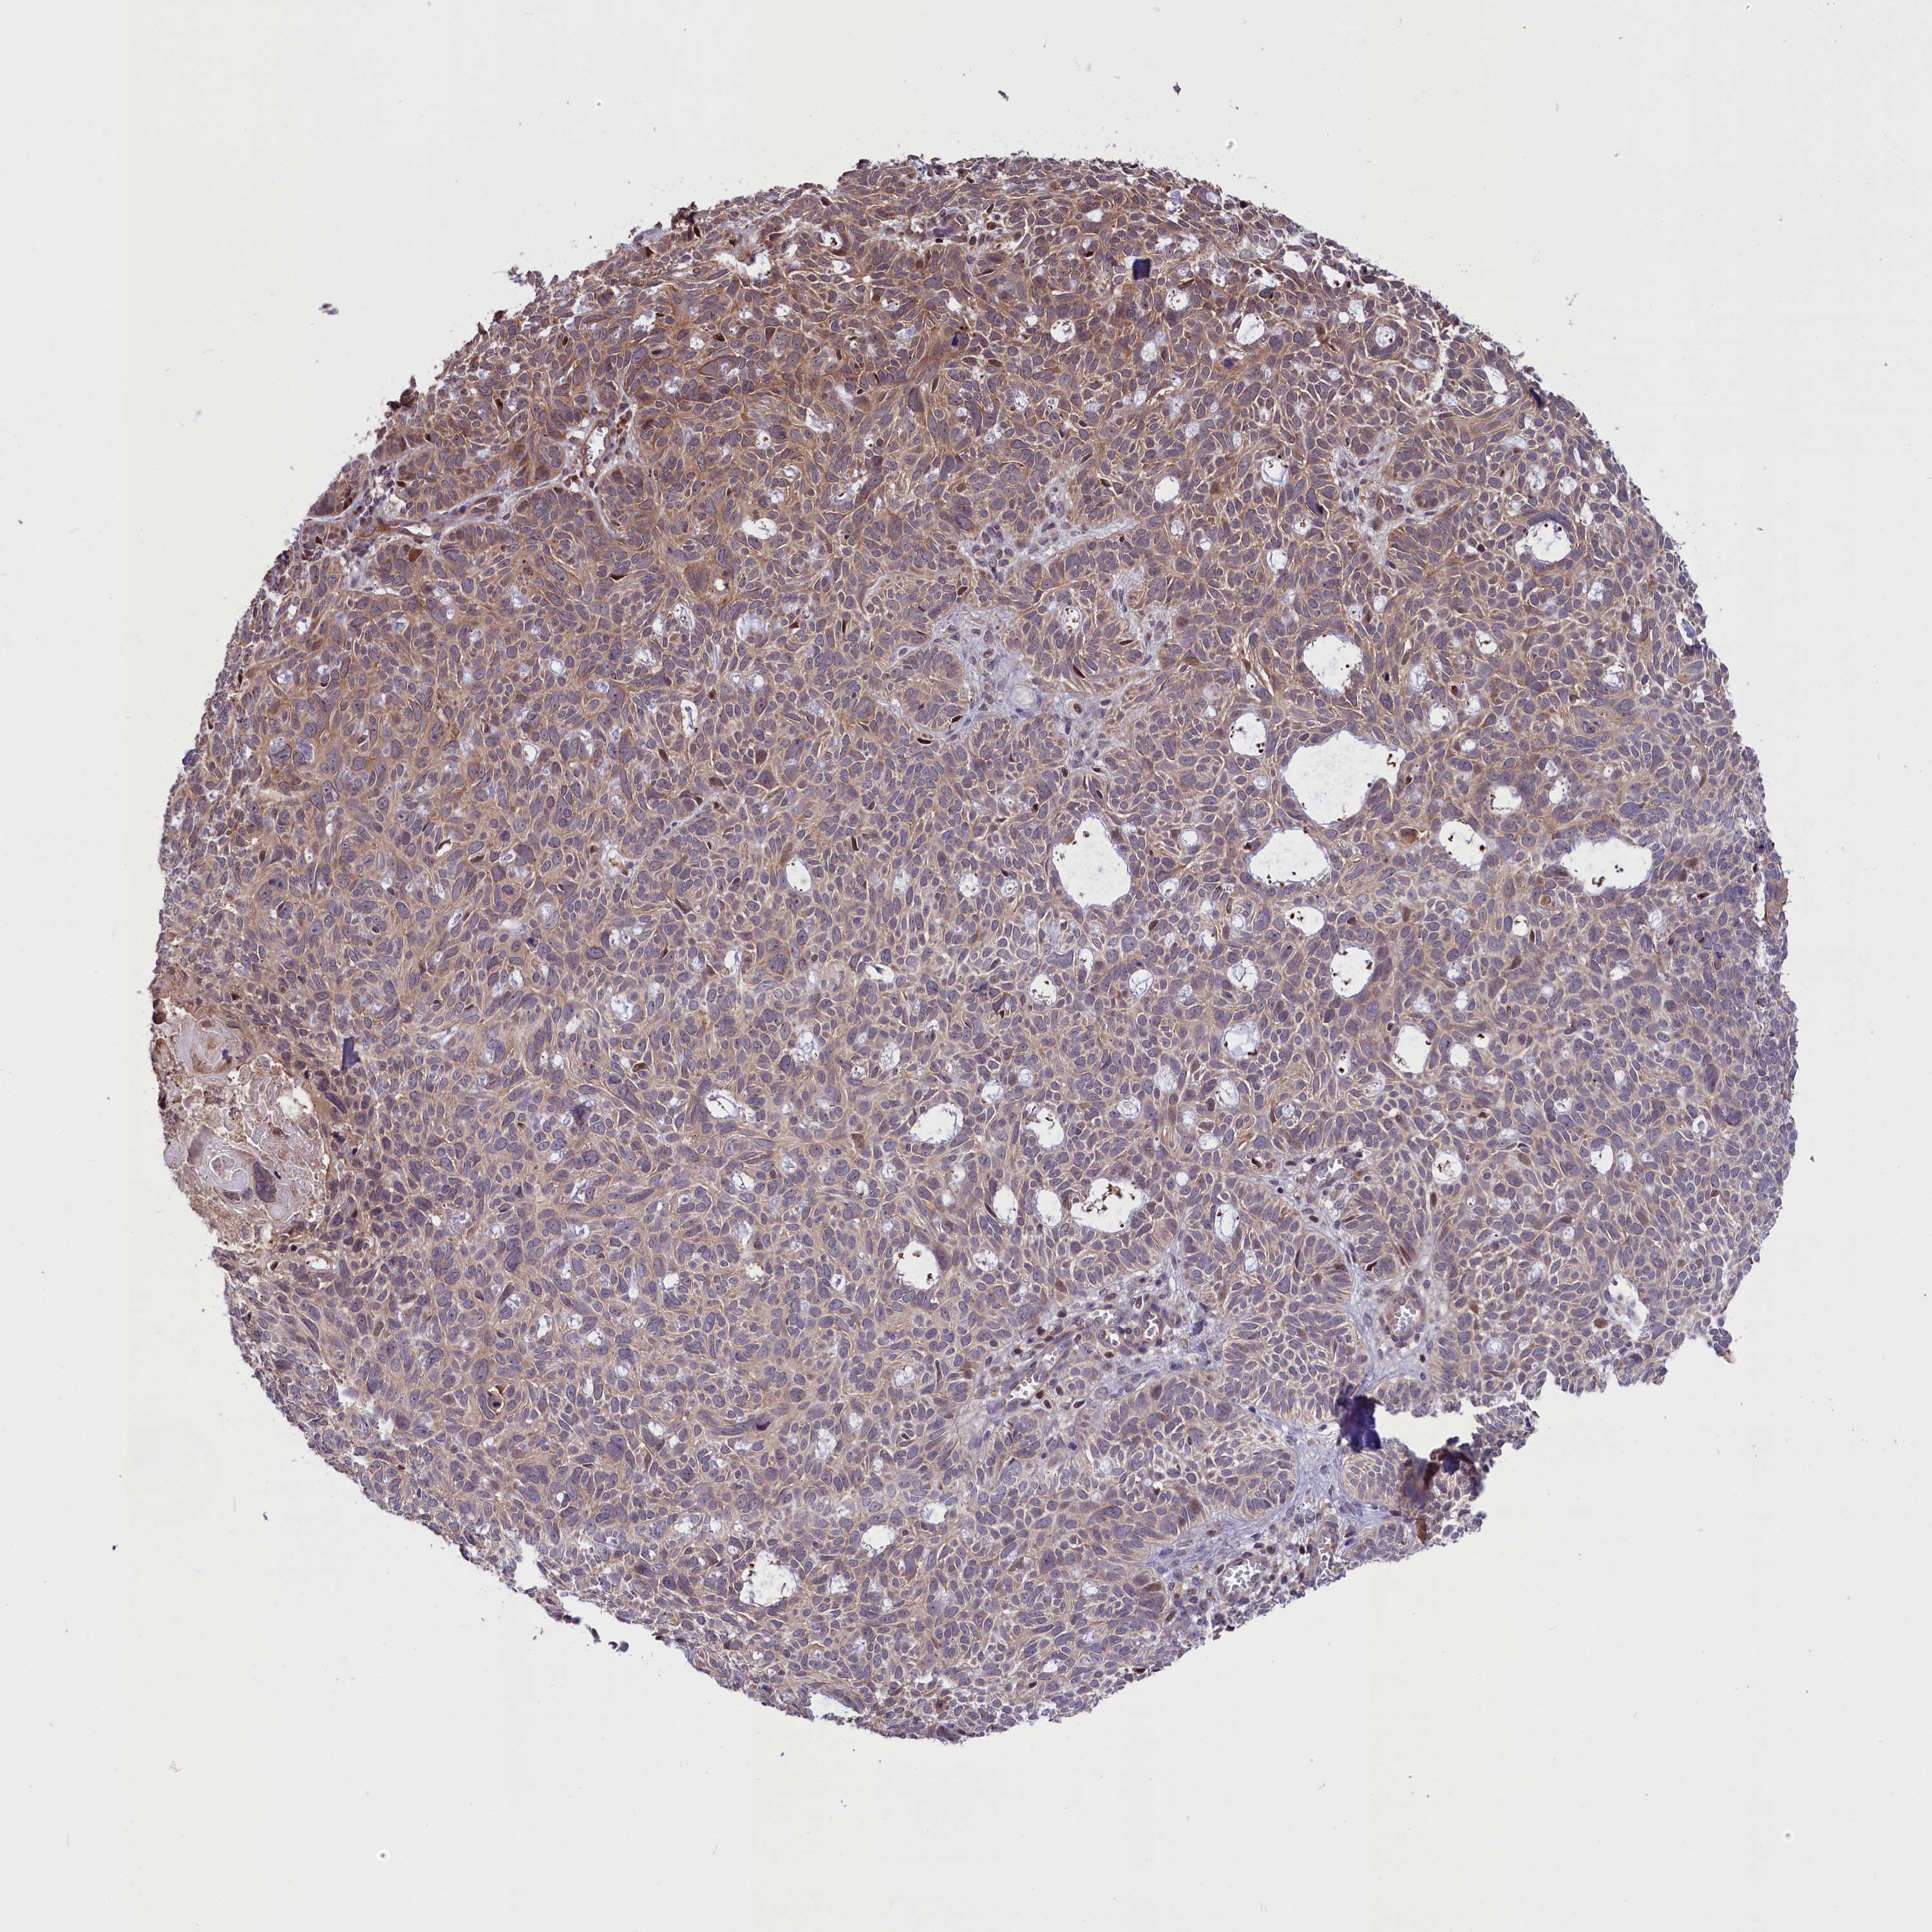

SKIN CANCER - Protein expressioni

A mouse-over function shows sample information and annotation data. Click on an image to view it in a full screen mode. Samples can be filtered based on level of antibody staining by selecting one or several of the following categories: high, medium, low and not detected. The assay and annotation is described here.

Antibody staining in the annotated cell types in the current human tissue is reported as not detected, low, medium, or high, based on conventional immunohistochemistry profiling in selected tissues. This score is based on the combination of the staining intensity and fraction of stained cells.

Each image is clickable and will lead to virtual microscopy that enables deeper exploration of all samples and also displays staining intensity scores, fraction scores and subcellular localization as well as patient and tissue information for each sample.

Antibody HPA041491

Antibody CAB046012

Basal cell carcinoma

Squamous cell carcinoma, NOS

Squamous cell carcinoma, metastatic, NOS